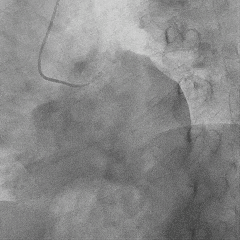

冠脉造影:

▶ LM未见明显狭窄;LAD近中段狭窄60%;LCX未见明显狭窄;RCA细小,未见明显狭窄。